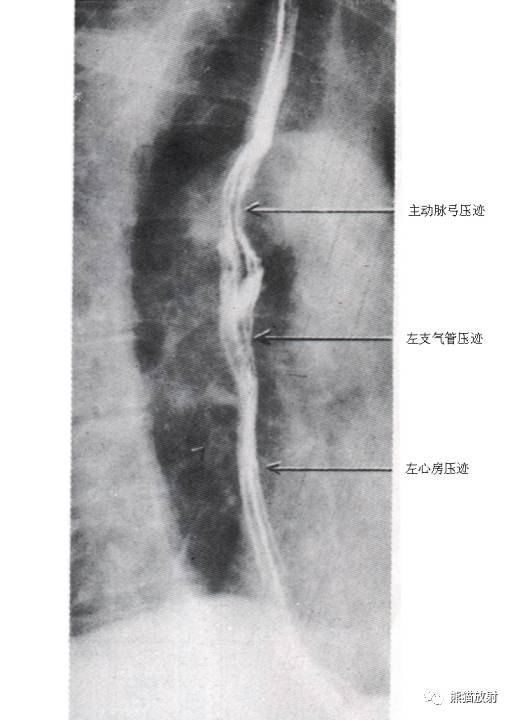

3 Esophagus 食管

1 Uvula 悬雍垂,2 Lateral glossoepiglottic fold 舌会厌外侧襞,3 Epiglottis 会厌,4 Piriform recess 梨状隐窝,5 Upper esophageal sphincter 食管上括约肌,6 Body of the esophagus 食管体部,7 Aortic arch 主动脉弓,8 Bronchial and aortic segment 支气管及主动脉段,A Paratracheal segment 气管旁段,B Aortic segment 主动脉段,C Bronchial segment 支气管段,D Interbronchial segment 支气管间段,E Retrocardiac segment 心后段,F Epiphrenic segment 膈上段